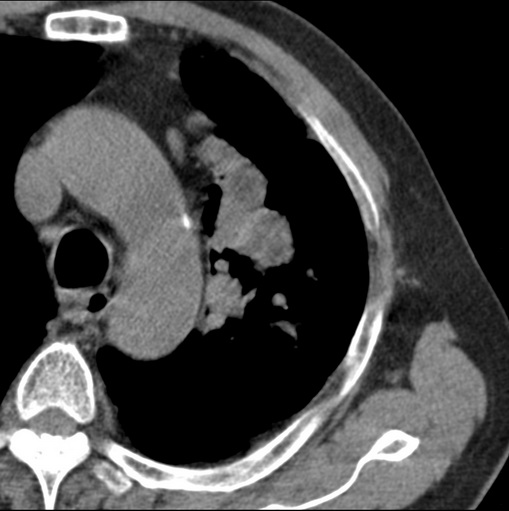

男性患者 81岁 咳嗽 咳痰 咯血

左肺中心型肺癌并:1.左肺阻塞性肺炎;2.纵隔淋巴结肿大;

考虑左上肺癌并阻塞性肺炎,左肺转移、左肺门及纵隔淋巴结转移。

标题: 考虑左侧中央型肺癌可能性大

肿块贴近左肺门,包绕左上肺动脉,形态不规则。肿块增强扫描中度强化。纵膈内主动脉弓左旁间隙、气管隆突前、下间隙见多枚淋巴结影。综上考虑左侧中央型肺癌可能性大。图片没有完整上传,尤其是左肺上叶支气管分支层面没有上传,因此不好判断是叶支气管中断还是段支气管中断。另外,下图红色部分所示是“黏液支气管征”吗?